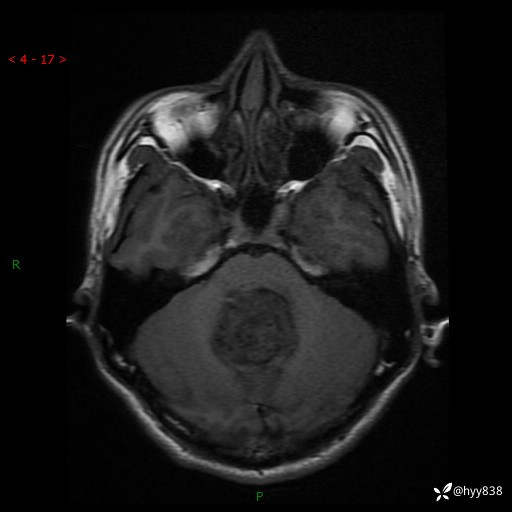

性别:男

年龄:17岁

简要病史:头痛伴间断性呕吐1月余,外院CT提示颅脑占位

颅脑MRI平扫+增强